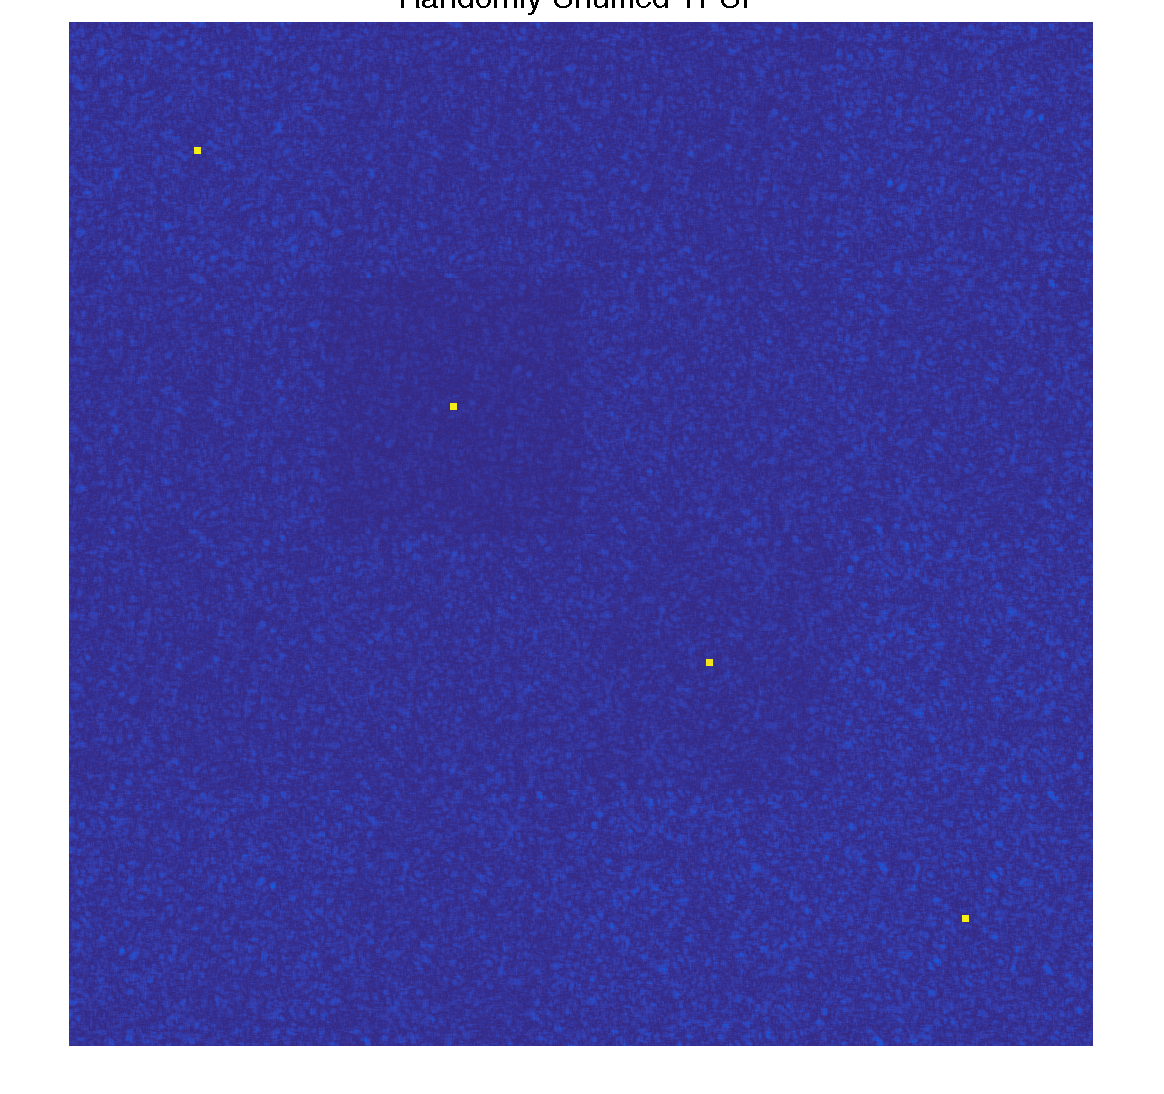

Simulate randomly shuffled ordering

The TPSF from randomly shuffled ordering shows a sharp peak, with incoherent artifacts that look like noise

mask_options.shuffle = true; mask = gen_t2shuffling_mask(mask_options); TPSF_rand = tpsf(mask, basis, K, patch_size); figure(3); imshow3(TPSF_rand), colormap('default'); ftitle('Randomly Shuffled TPSF', 32);